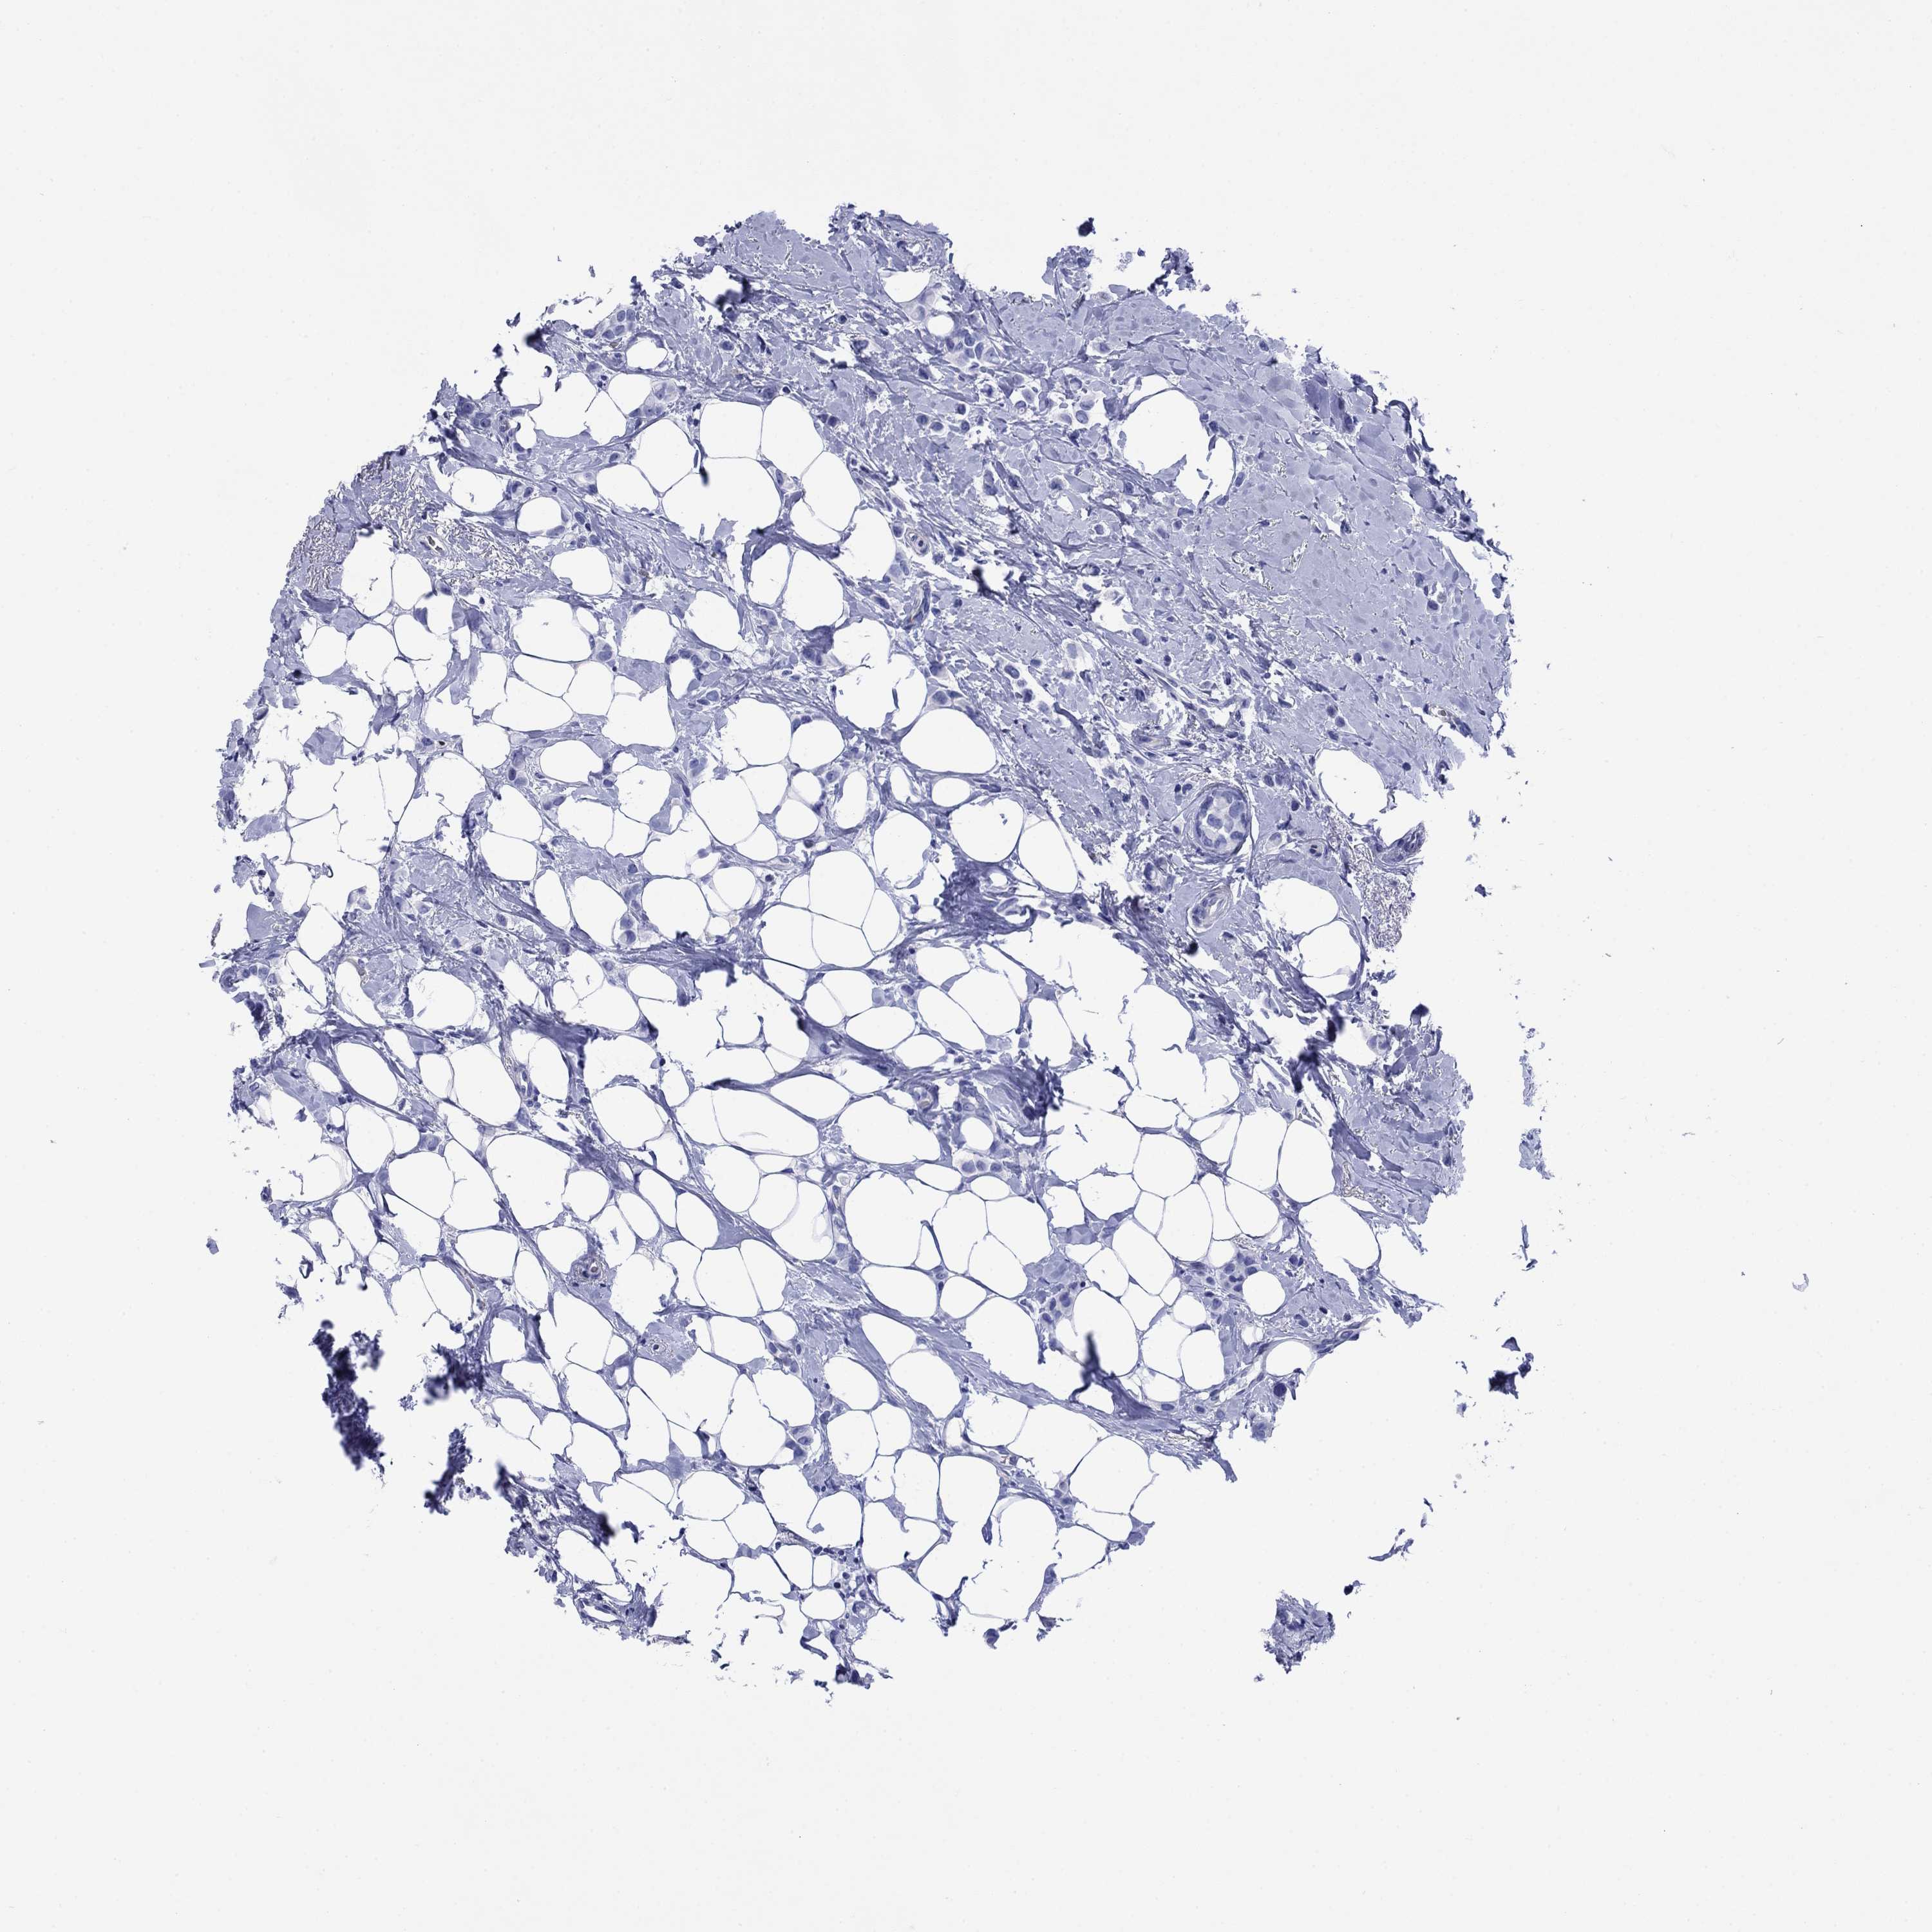

CANCER BREAST CANCER Show tissue menu

Breast cancer

Human cancer